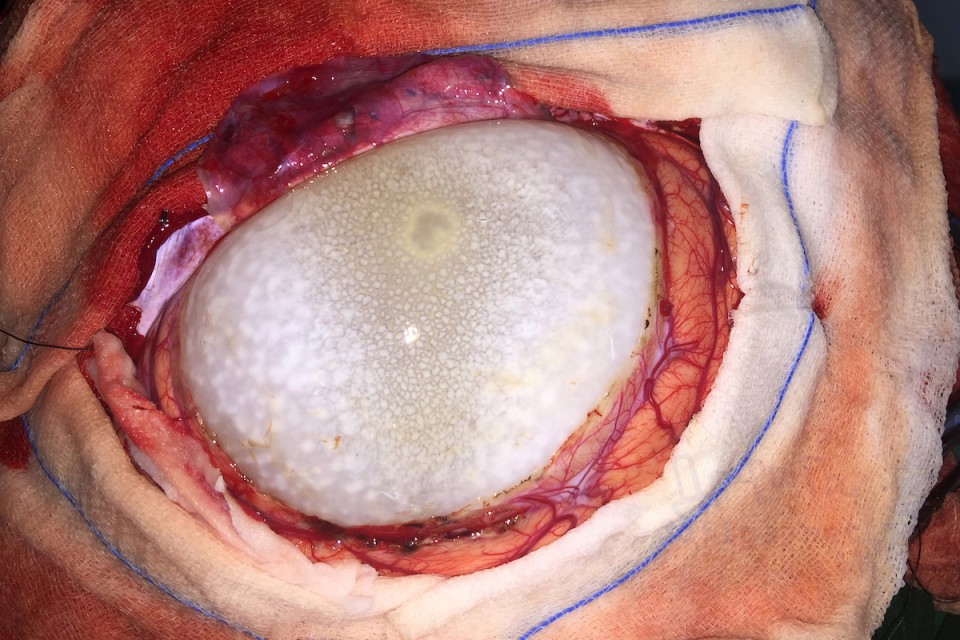

gif_animation インドにて、12歳の女の子の身体(脳部分)から、寄生虫の卵、675gが取り出された。頭痛に苦しんでいたという女の子。感染源は不明である。[7]images